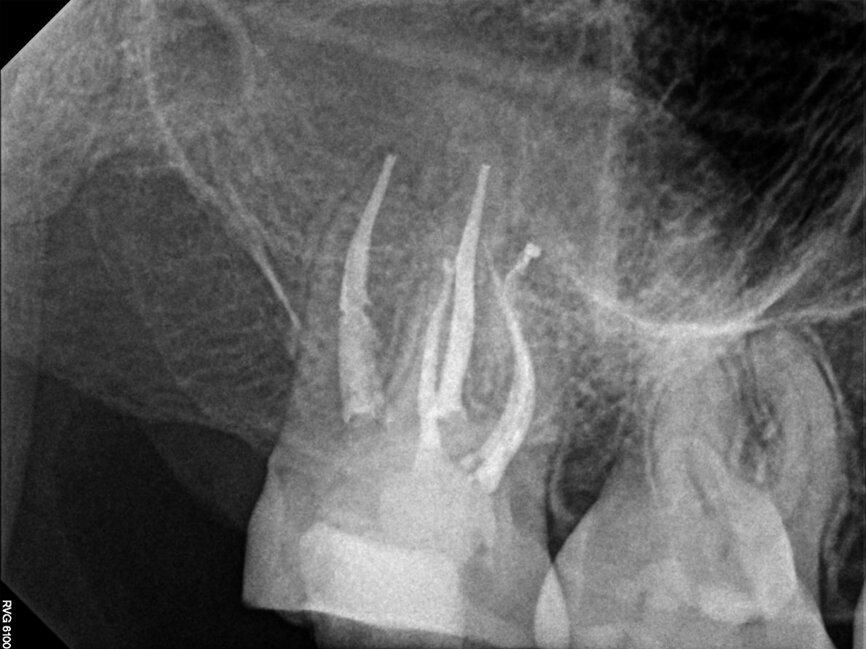

Fig. 14a: Case treated with Bassi Logic controlled memory nickel titanium files. Note the visualization of the third root on this lower molar and conservative canal preparation shape. (Courtesy of Dr. Alex Chan)

Fig. 14b: Case treated with Bassi Logic controlled memory nickel titanium files. Note the visualization of the third root on this lower molar and conservative canal preparation shape. (Courtesy of Dr. Alex Chan)